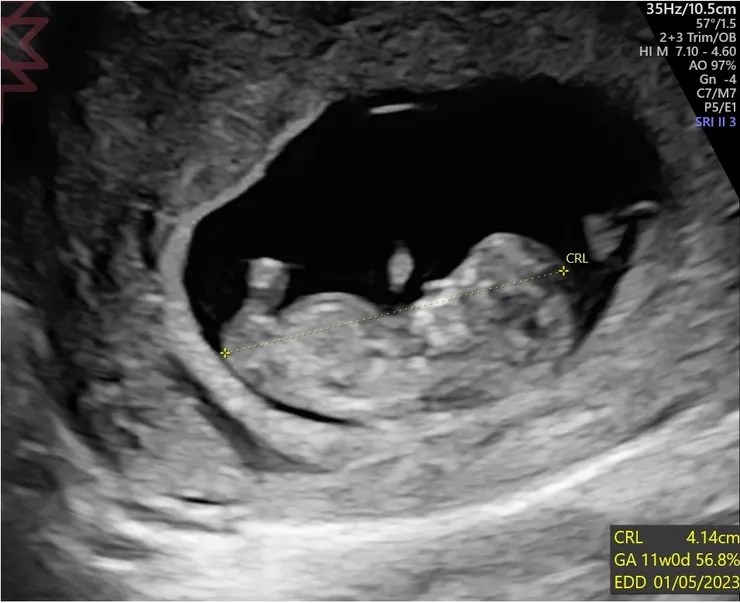

第九週的第一天吧,原本要去上課的我臨時取消,因為前晚突然吐了兩次,讓我進入另一個害怕的狀態。那天一早就掛了員基,醫生照例會先照超音波,在問診時我突然感覺失去語言能力,間斷地說我無法吃東西......也不太能喝水......吃了藥就會吐,醫生淡淡的說,通常是懷孕12週前會孕吐。這句話,我從第一天上網查就知道了,後來遇到的兩位醫生也都說了同一句話,然而當時已經受苦一個月的我,聽到樣板式的答案只感到既無助又絕望,醫生表明能做的不多,我彷彿一人墜身無底黑暗,已經身心俱疲、陷入憂鬱、度日如年的我,如何能再過三週?頓時眼淚奪眶而出,不斷隱沒入口罩的上緣,醫生瞥見似乎露出些微訝異的眼神,我不曉得他能不能看見眼中的不斷墜落的無助。

進入第十一週後,在這個規律之上出現了新症狀,有天突然開始分泌很多口水,上網查這也是懷孕賀爾蒙影響的症狀之一。把口水吞下去容易噁心,只好幾分鐘就去吐掉,這也是伴隨著傍晚不適而出現的,躺在床上必須經常吐掉有點煩人,但比起噁心反胃嘔吐算是小怪一隻。另外一隻小怪是體溫變化,晚上十點左右手掌腳掌會變得很熱像是發燒,也會伴隨更明顯的不適,只能翻來覆去,調低冷氣溫度,但睡到凌晨後又太冷流鼻涕。